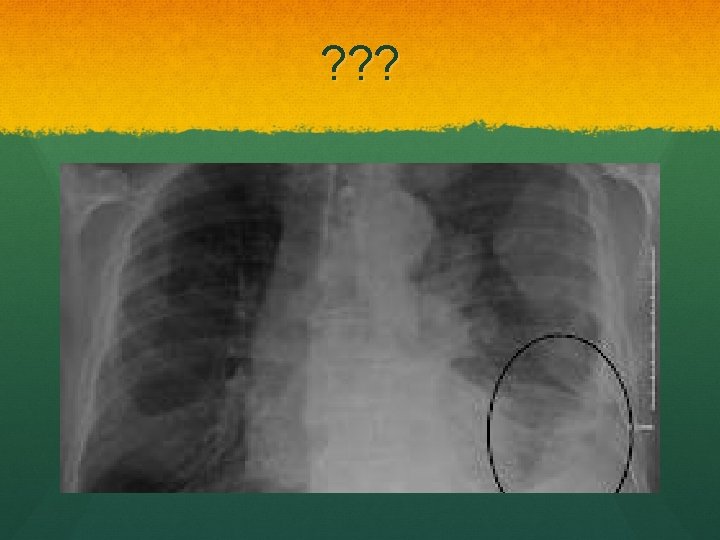

Asbestosis Inhlation of asbestos Plumbers, electricians, builders Blue asbestos (crocidolite) Can’t be cleared by immune system Histology: asbestos bodies and features of pulmonary fibrosis, affecting lower lobes more

Rx No treatment Considerable time lag: 20 -40 years following exposure Compensation Risk……….